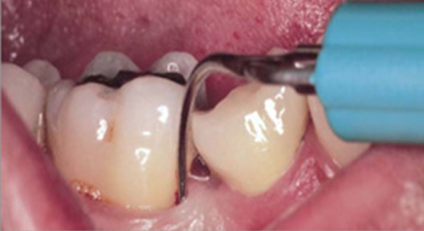

Ultrasonic debridement has other advantages as well, including cavitation. Inserts of different shapes enable the practitioner to maximize intimate contact between the insert and the root surface (Figure 3 and Figure 4). The vibration of the tip mechanically interrupts the etiology in all of its forms and also exerts the cavitational effect, the energy that is imparted through the frequency of movement, and the millions of tiny bubbles that form and then implode the released energy. While there is some debate about whether that energy kills bacteria, there is complete consensus that cavitation has the ability to disrupt biofilm beyond the insert tip.18

Therefore, with ultrasonic instrumentation, it is possible to widen the area of debridement, making it more likely to maximize the chance of removing the etiology, including microscopic as well as visible and tactile calculus and plaque (Figure 5).

Fig. 3 and Fig. 4 Examples of various ultrasonic tips allowing maximal contact between the device and the root surface to optimize the cavitational effect in disrupting biofilm.

Figure 3

Figure 4